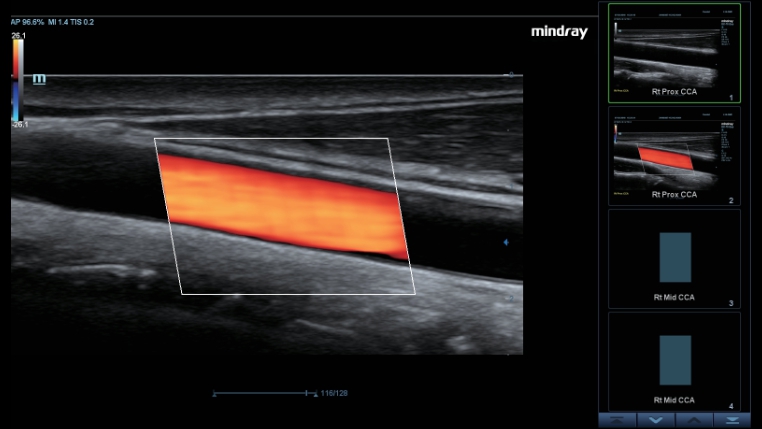

Trasduttori ComboWave

ComboWave utilizzano un nuovo tipo di materiale piezoelettrico composito per ottimizzare efficacemente lo spettro acustico e ridurre l'impedenza acustica. Se integrati con la tecnologia 3T, distintiva di Mindray, i trasduttori lineari ComboWave garantiscono prestazioni eccezionali con risoluzione dâimmagine e uniformitĂ eccezionali nelle applicazioni relative a tiroide, seno, vascolari e altro ancora.

Smart Track

Con un semplice tocco, Smart Track consente di ottenere una visualizzazione ottimizzata rapida e intelligente dell'imaging vascolare. ? in grado di ottimizzare lo spettro del colore, del power e del PW mediante il funzione di tracking automatico e ridurre i passaggi che richiedono molto tempo, semplificando cosĂŹ il flusso di lavoro per gli esami vascolari.